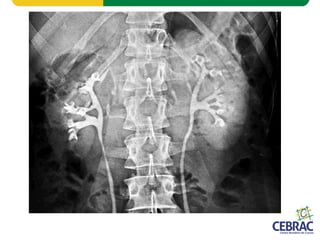

Aorta Veia Cava

2 Ureteres

• Sistema Urinário

– Dois rins

– Dois ureteres

– Uma bexiga urinária

– Uma uretra

Córtex

MedulaRim Esquerdo

Rim Direito

Bexiga

Uretra